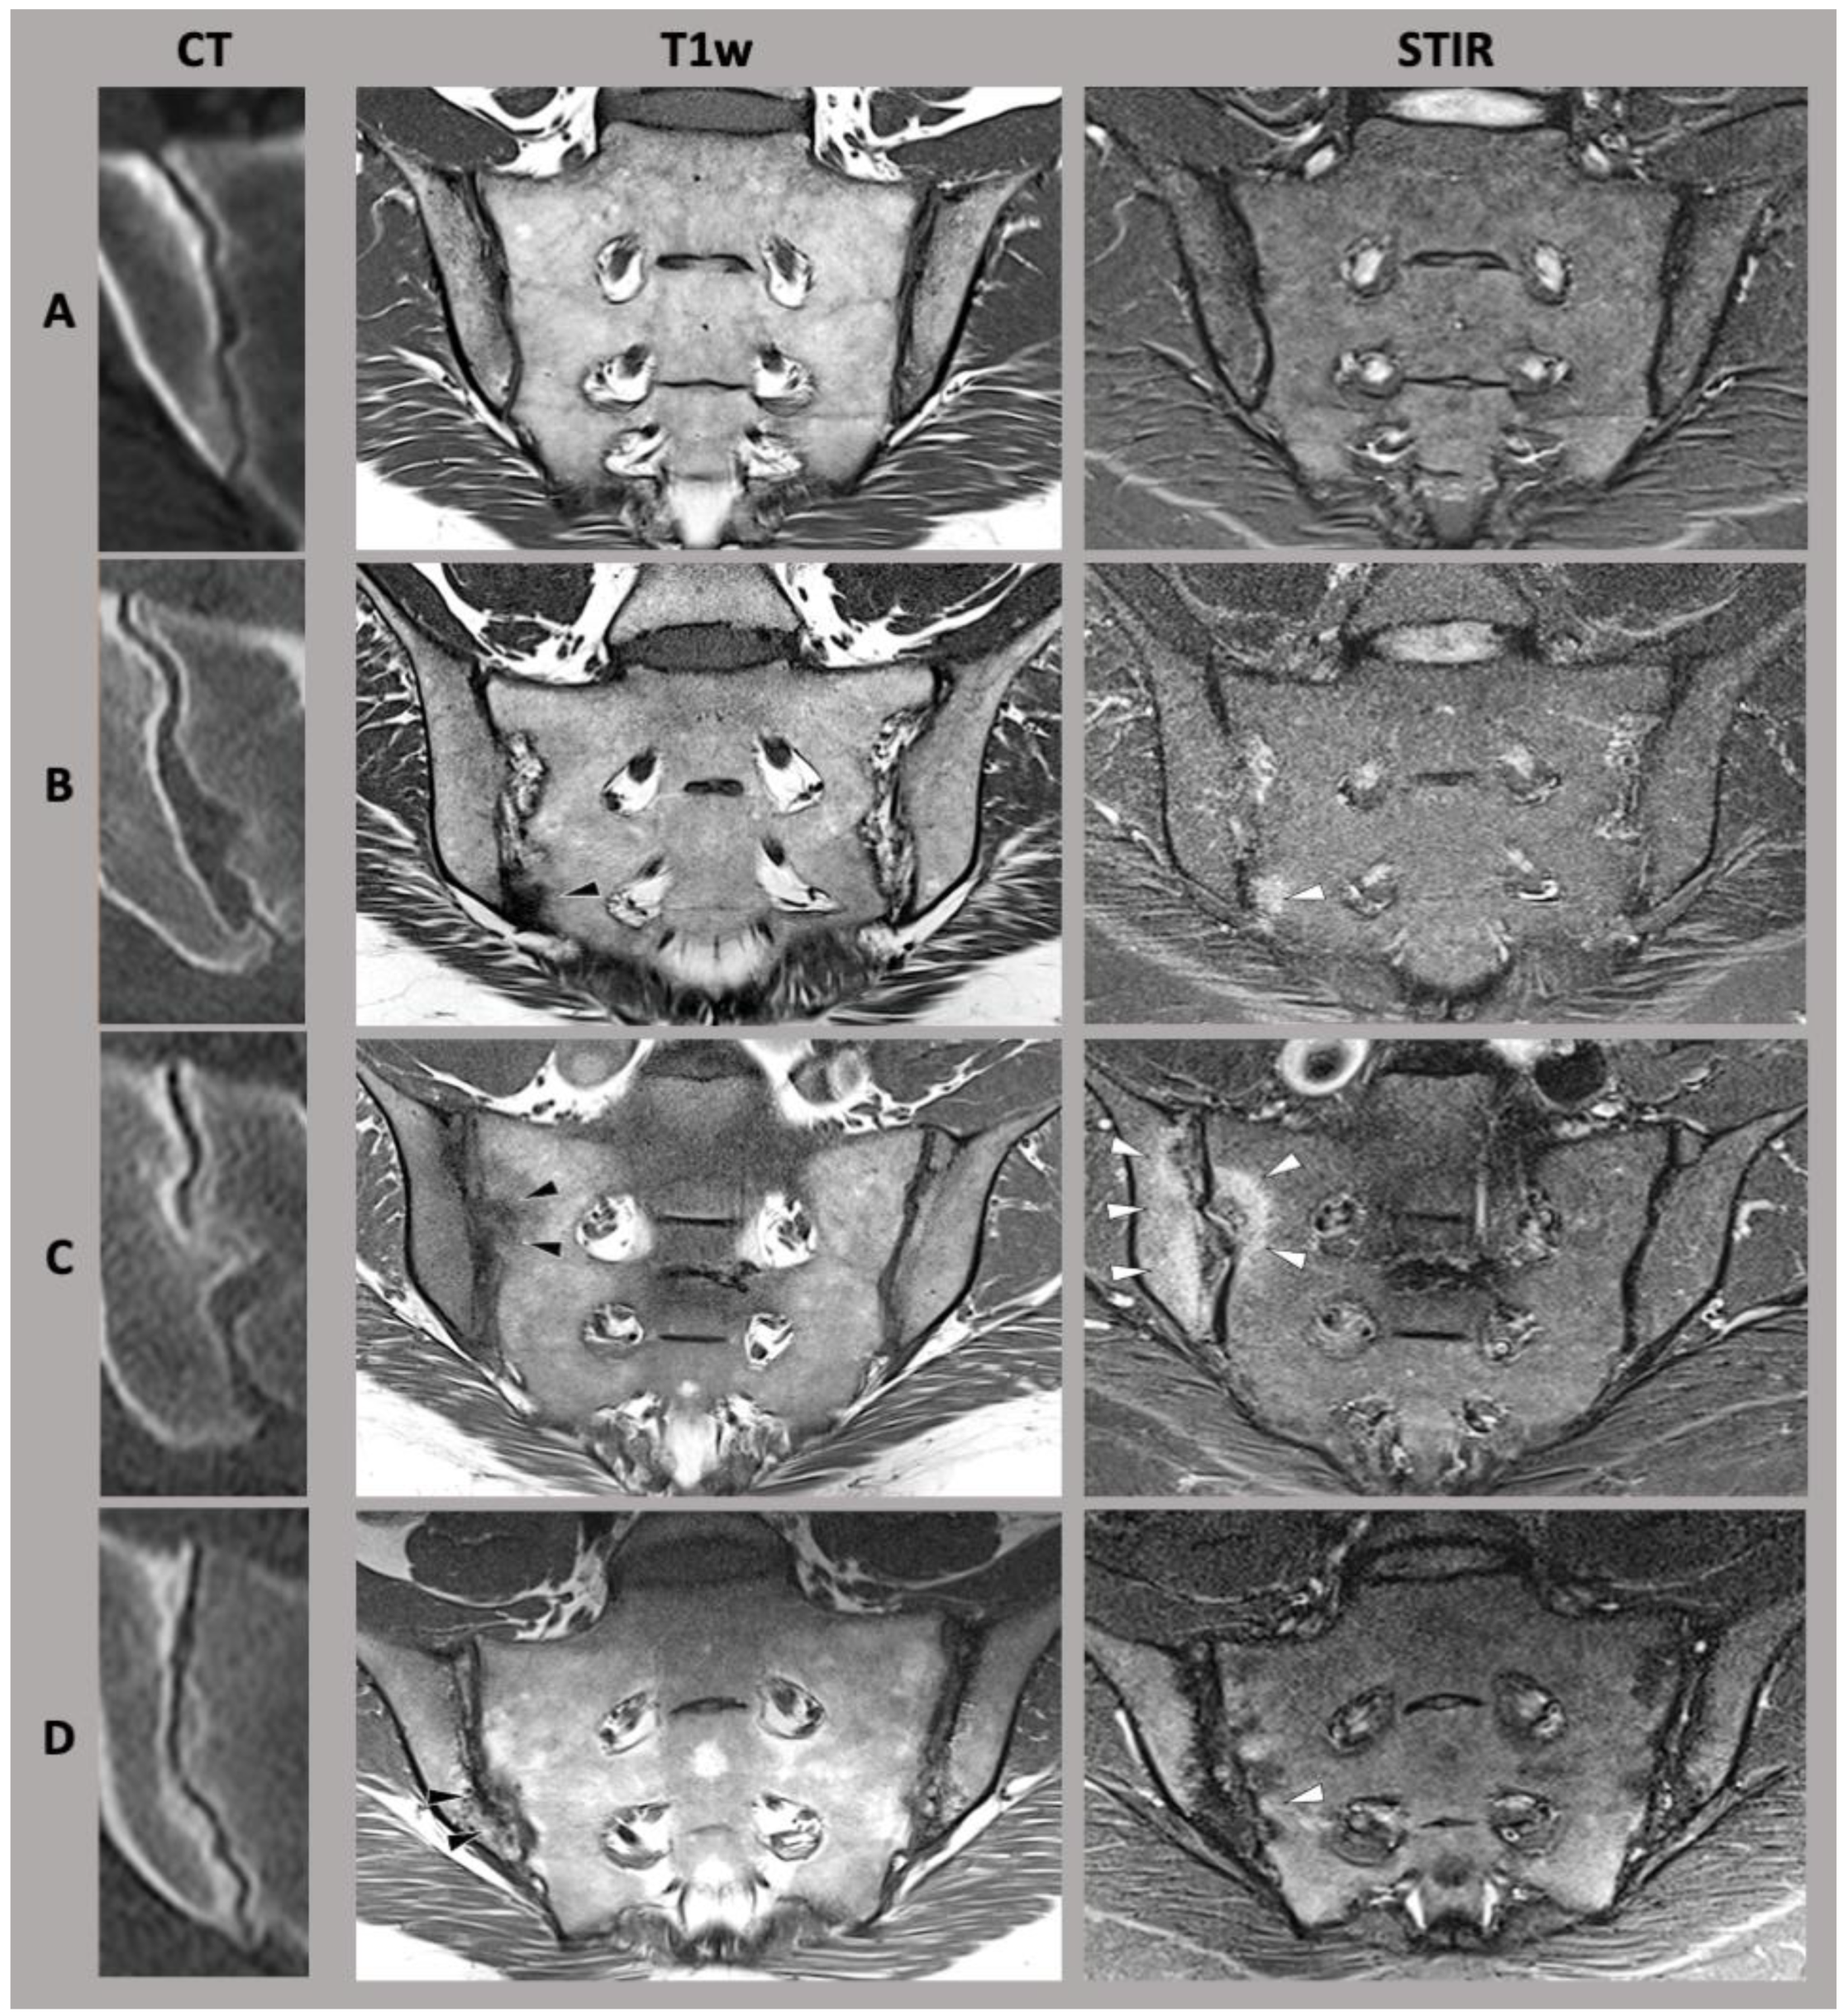

Initial attempts at differentiation of joint shapes have been evaluated in detail by Prassopoulos et al. [23]. In their work, they distinguished six different shape variants of the SIJ as follows: the accessory joint facet, typically located dorso-inferiorly to the main joint; the sacroiliac complex, which constitutes a convex bulge of the ilium, corresponding to a concave sacral facet; the bipartite iliac bone plate, which may look like a slim bony defect parallel to the joint in its dorsal part; the crescent-shaped ilium, which leads to an overall more saccular shape of the sacroiliac joint; semi-circular notches (also referred to as “defects”) on both iliac and sacral side of the joint; and sacral ossifications center, typically located at the ventral portion of the joint [23] (also see Figure 1).

Figure 1.

A selection of sacroiliac joint form variation. (CT) computed tomography, (T1w) T1-weighted magnetic resonance imaging sequence, (STIR) short-tau inversion recovery magnetic resonance imaging sequence. (A) typical sacroiliac joint form, (B) accessory joint facet, (C) sacroiliac complex, (D) crescent-shaped ilium. Adapted with permission from Refs. [6,24]. Copyright 2021-22, copyright Katharina Ziegeler.

Of particular importance are shaped variants associated with altered biomechanics [8]. Initial studies suggest that these have some association with chronic degenerative changes of the SIJ, possibly due to increased mechanical stress or altered relative movement and therefore differences in load distribution [6]. In addition, shape variants are also associated with an increased likelihood of the occurrence of inflammatory changes at the SIJ. SIJ form variation is especially common in patients with lower back pain along with symptomatic joint disease [7,24].